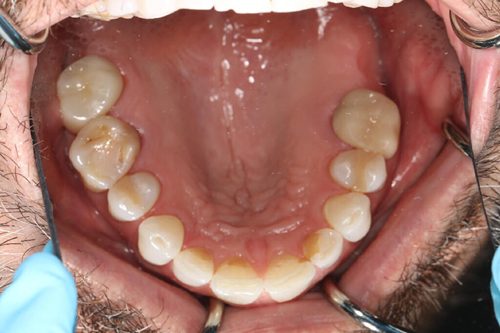

A male patient underwent tooth-colored fillings and dental crowns by Dr. Jeffrey A. Weller in Chicago, IL, in May 2018. Following the procedures, the patient reported a positive experience, expressing satisfaction with the results. The clinical team’s meticulous work and Dr. Weller’s expertise were highlighted, contributing to a successful outcome. The patient left the clinic with improved dental health and a confident smile, grateful for the professional care received.

After